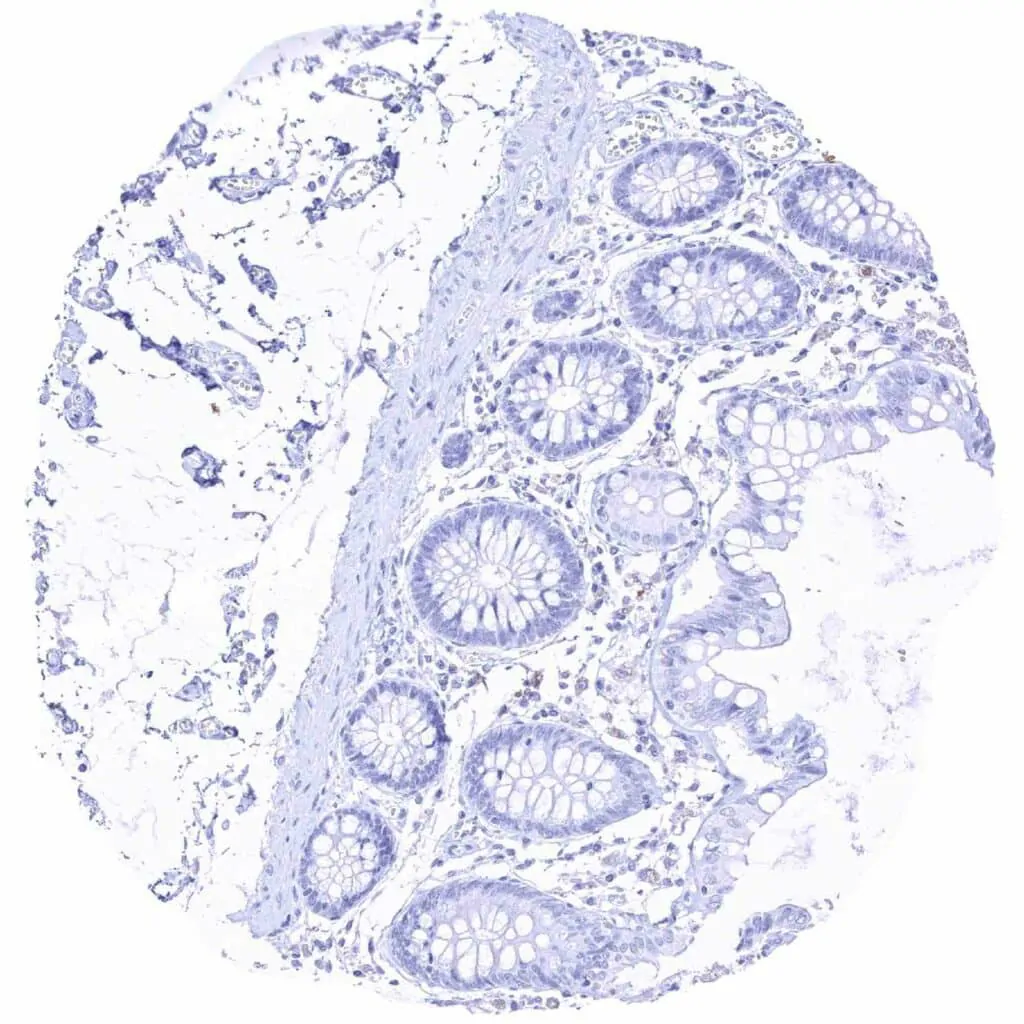

Rectum, mucosa